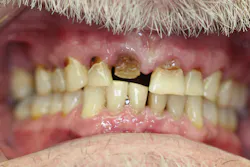

Upon receiving approval from his oncologist to commence with dental care three months later, his examination revealed the following (figures 1-5):

- Severe class III active periodontal disease

- Rampant, generalized cervical caries with some lesions quite extensive in nature

- Broken no. 8 (chief complaint)

- Broken/carious nos. 18, 19, and 30; caries on no. 2

- Generalized dry mouth with white patchy mucosa; he did have a complaint of having a “sticky mouth.” Note: When we took the photos, we had to put water in his mouth because it was so dry.

The genesis for his caries was evident–drug-induced dry mouth and time were the perfect storm for widespread infection that demanded immediate management. Suffice to say, my news to the patient was not welcome.